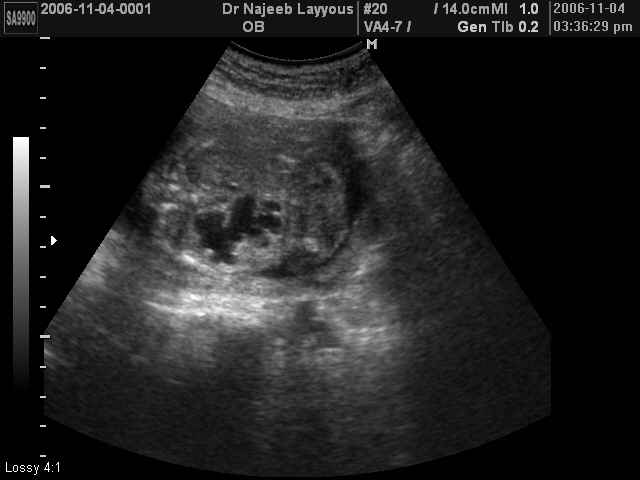

صور طبية للحمل بجهاز الالتراساوند | الدكتور نجيب ليوس